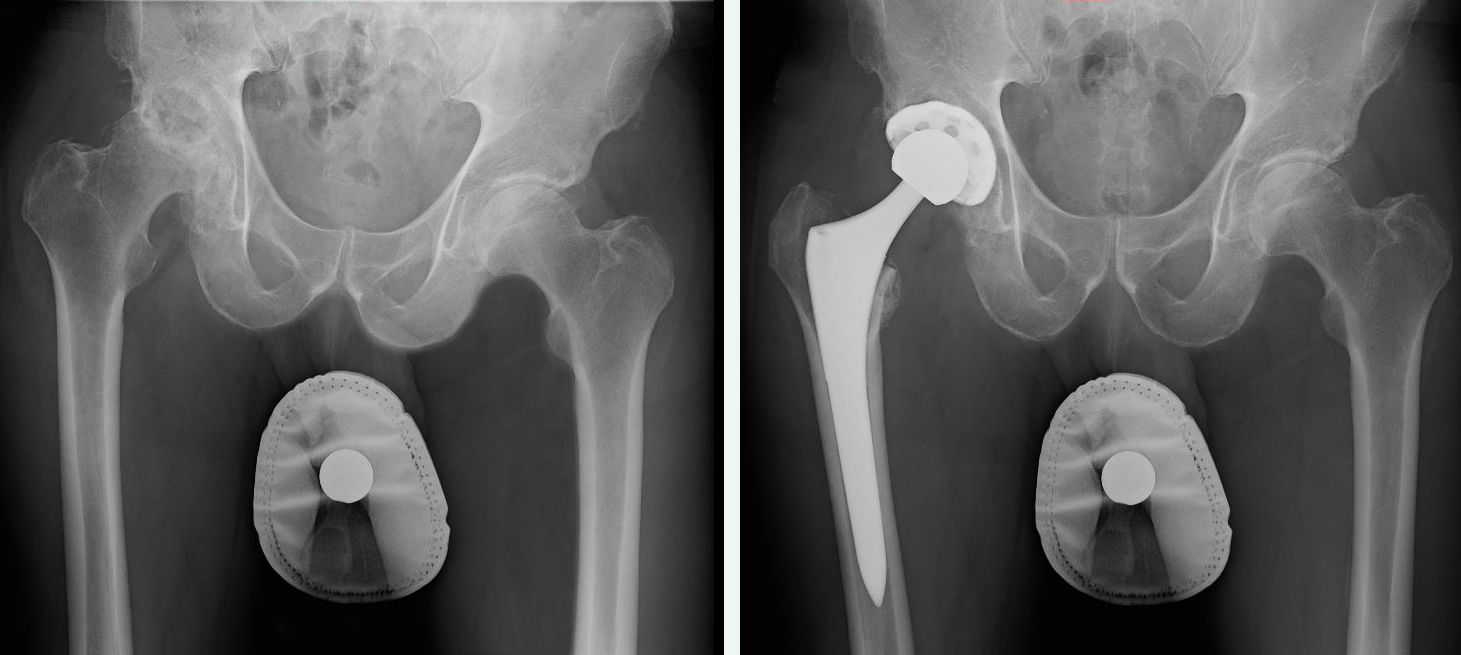

Hip replacement surgery, also known as hip arthroplasty, is a medical procedure primarily prescribed for individuals experiencing chronic hip pain, hip arthritis, limping, or lower extremity weakness. This surgical intervention becomes necessary when the hip joint has suffered damage, typically due to degenerative conditions or traumatic injuries. The ultimate goal of hip replacement surgery is to restore joint function and mobility by replacing the damaged hip joint with artificial implants.

Orthopedic surgeons typically recommend this surgery to patients who are grappling with severe hip joint arthritis or necrosis, which has rendered them bedridden due to unbearable pain and instability in the joint. During the surgical procedure, only the affected portions of the hip joint are removed, whether that entails a partial or complete joint replacement.

The overarching objective of hip replacement surgery is to enable individuals to regain their ability to engage in daily activities and exercise without the hindrance of pain, ultimately improving their quality of life.